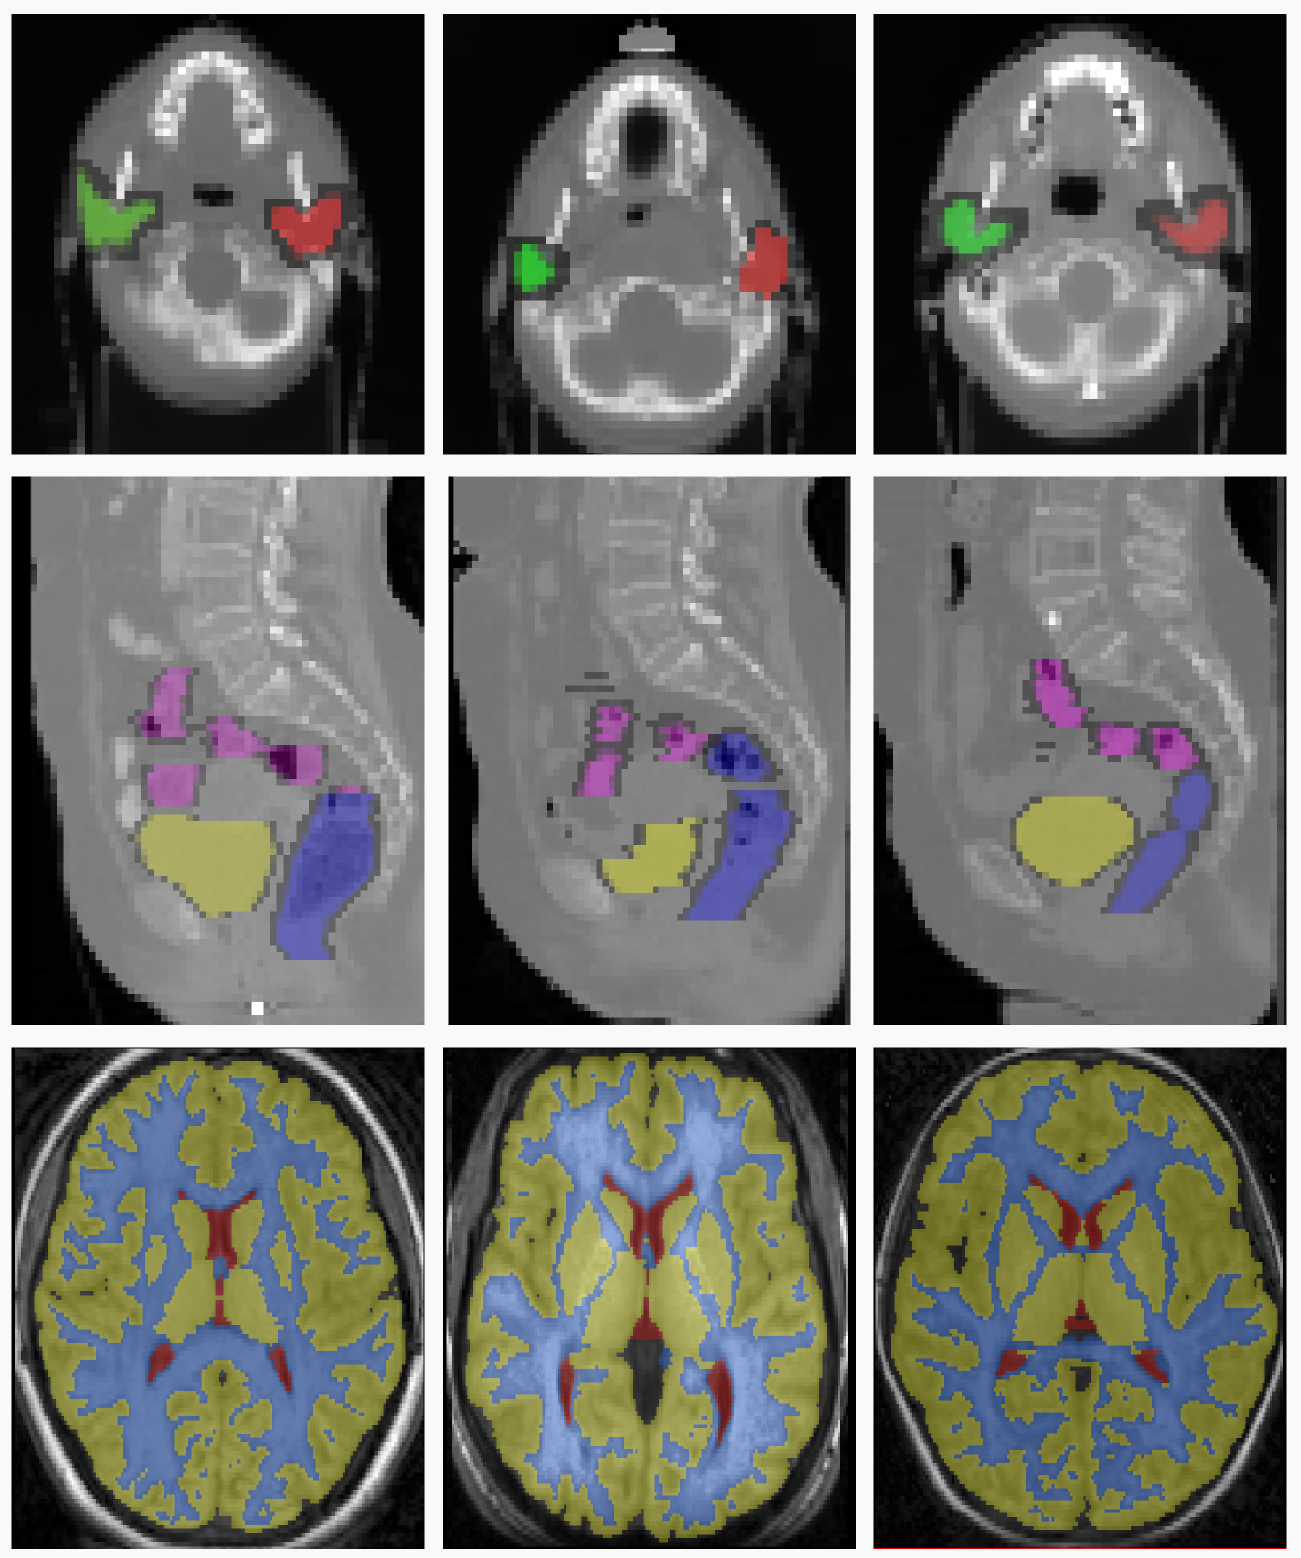

Below we show visual results on three datasets used as a proof-of-concept for our proposed method, to highlight the effects of learning the weights of different metrics for the task of deformable registration.

Refer to caption

Figure 3: Sample slices from three different volumes of the RT Parotids, RT Abdominal and IBSR datasets.The top row represents the sample slices from three different volumes of the RT Parotids dataset. The middle row represents the sample slices of the RT Abdominal dataset, and the last row represents the sample slices from the IBSR dataset.